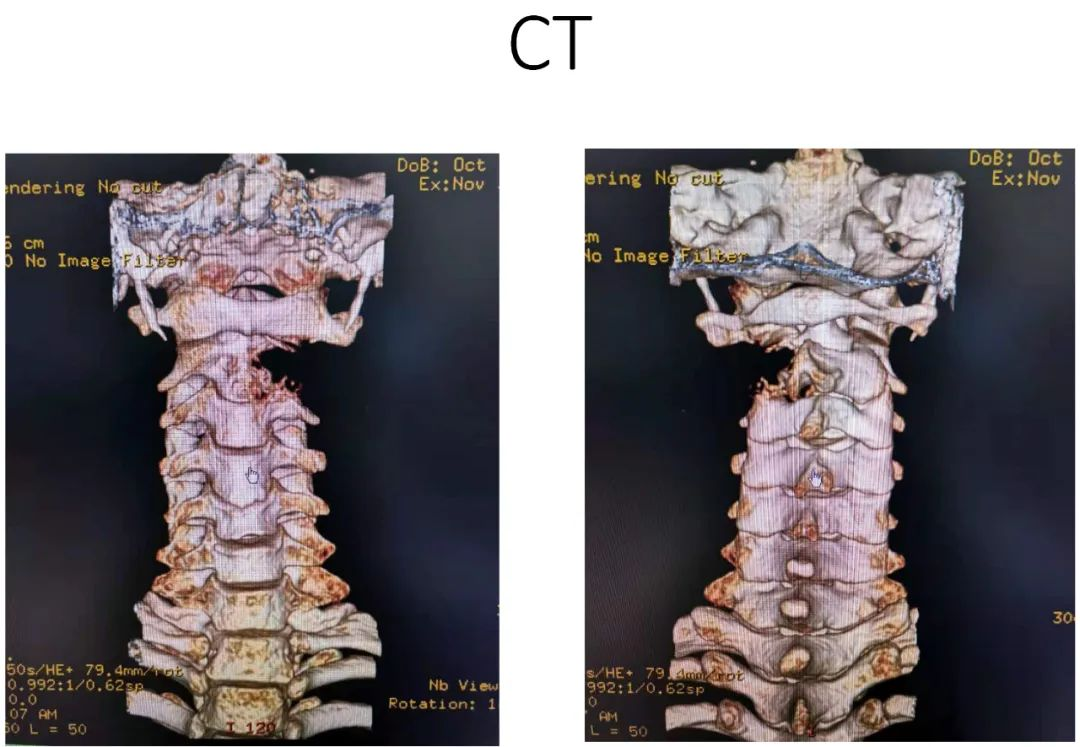

病史:male, 63 y/o

Neck pain for 3 months

影像资料:

诊断:C2椎体肿瘤